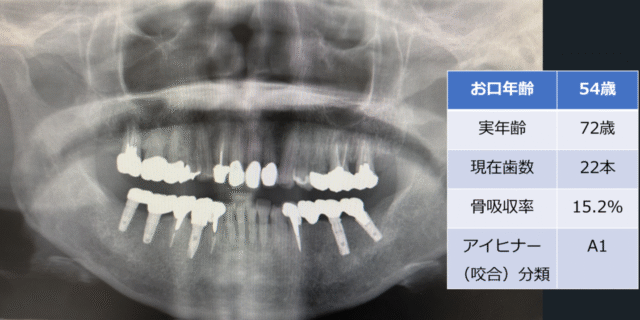

「お口年齢AI」は、歯科パノラマエックス線画像から、現在歯数、インプラント数、アイヒナーの咬合分類、歯槽骨吸収量(歯周病年齢)などの抽出したデータと、生年月日・性別の情報から、「お口年齢」を算出するシステムとなっています。

本システムでは、生活習慣病である歯周病に関連する歯槽骨吸収量(歯周病年齢)も加味して判定します。

また抜歯後にブリッジやインプラント治療を行った場合などは、顕著に「お口年齢」が若年指標として算出されます。